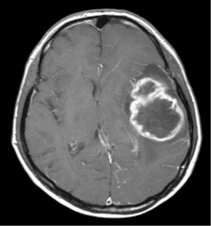

Gliome entwickeln sich aus den Stützzellen des Gehirns. Diese Zellen werden Gliazellen genannt. Von den unterschiedlichen Arten dieser Gliazellen leiten sich die Arten der Gliome ab. Es gehören z. B. Astrozytome, Oligodendrogliome oder Ependymome dazu. Astrozytome sind die häufigsten Tumore.

Die aggressivste Form des Glioms ist das Glioblastom (Glioblastoma multiforme). Es wächst schnell und infiltriert das umgebende gesunde Hirn.

Die Gliome werden von der Weltgesundheitsorganisation WHO im Hinblick auf ihre feingewebliche Struktur und ihr Wachstumsverhalten in 4 Grade (WHO I bis IV) eingeteilt.